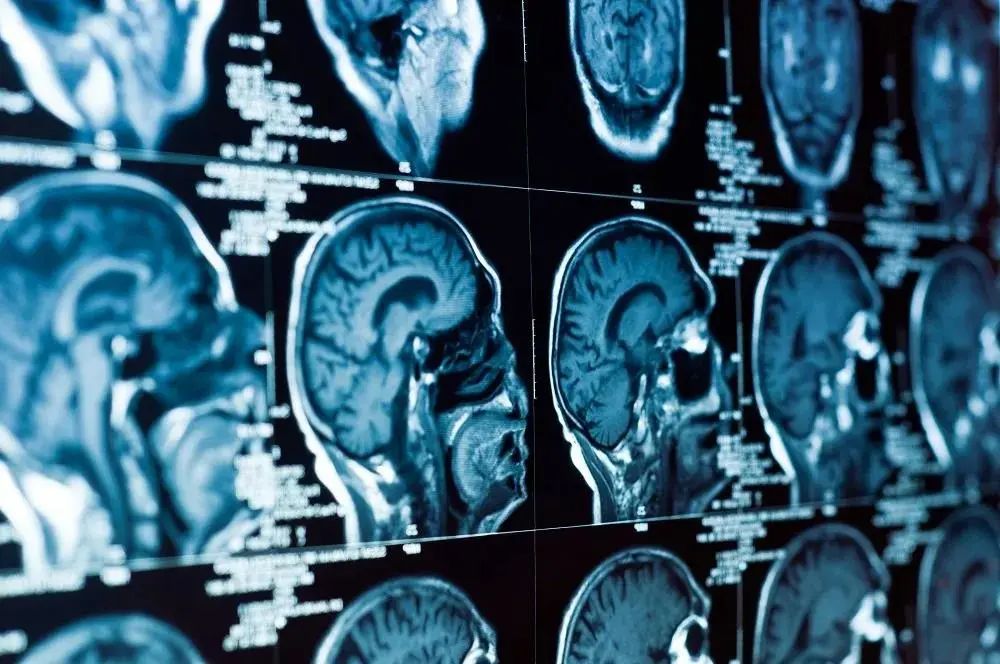

我的认知取决于我的神经元——我的大脑细胞。更准确地说,我所知道的取决于数百亿神经元之间的具体连接方式,取决于相连神经元之间的神经化学相互作用,以及不同类型神经元的反应组合。所有这些让我成为了我。

而神经元是这一切的根源,它们是如何让我们知道这一切的?

- Akira Kusaka -信息分布于神经元中

正如后来改进的实验方案表明的,拉什利的非定位结论基本正确。大脑中没有专门的记忆器官,信息根本不是存储在特定的文件柜中,而是分布在神经元中。

神经科学家正试图使用多种研究策略来理解学习的结构。一种策略包括在神经元水平追踪依赖于经验的变化,用以找出究竟是什么、在什么时候以及为什么发生变化。另一种策略涉及更大范围的学习:当身体受到损伤时,或在发育过程中,或当受试者在扫描仪中执行记忆任务时,或当实验动物的某些基因被敲除时,行为和特定的大脑子系统会发生什么?在这个研究层面,心理学、神经科学和分子生物学紧密合作。

大脑里发生了哪些依赖于经验的调整呢?每一天,这些神经元共同造就了现在的我,它们经历着许多结构上的变化:新的分支会冒出,已有的分支会延伸,新的神经化学信号的受体位点会形成。另一方面,修剪会减少分支,从而减少神经元之间的突触连接数量;或者,剩余分支上的突触可以被完全关闭;或者,整个细胞可能会死亡,伴随而去的还有它所支持的所有突触;或者,最后在某个特殊区域,一个崭新的神经元可能会诞生,开始在该区域建立突触连接。

这还不是全部。重复高频的突触放电(尖峰)会耗尽可供释放的神经递质囊泡,从而构成一段约2~3秒的记忆。特定神经元的成分、每次峰电位释放的囊泡数量,以及每个囊泡中包含的递质分子数量都可以发生改变。然而,不知何故,尽管我的大脑每一天、甚至每一分钟都并非完全相同,但我的技能几乎保持不变,我的自传体记忆依然完整。